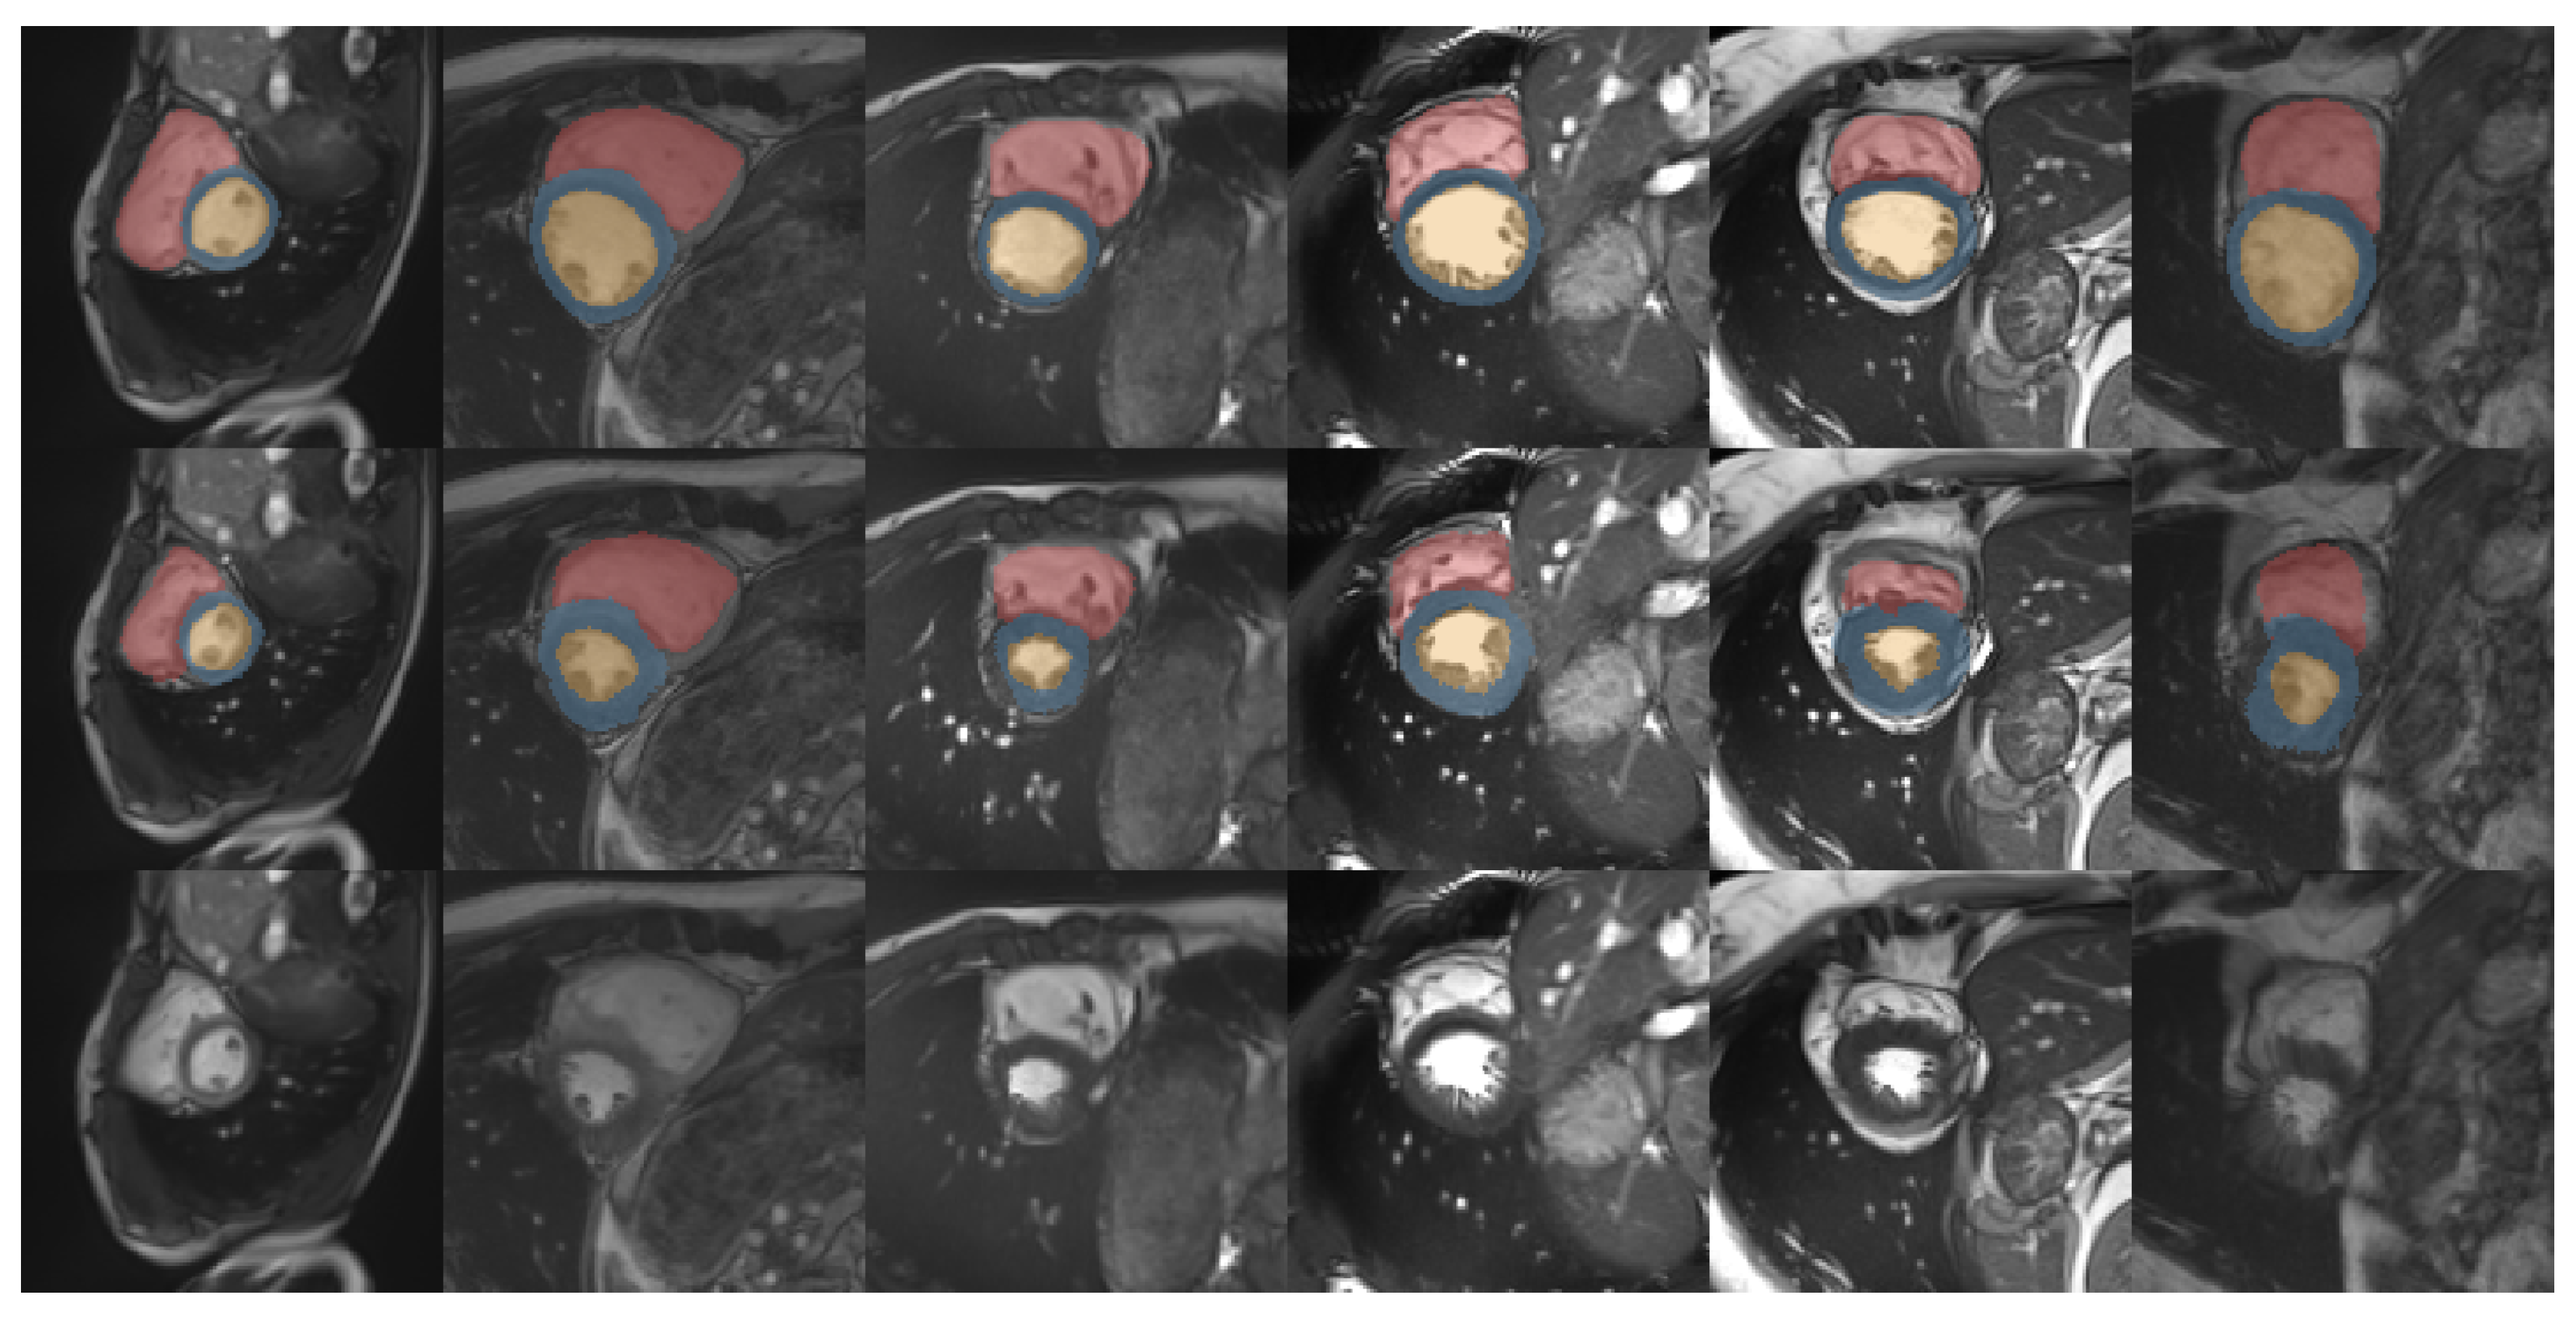

3.3. Medical Cardiac Image Registration